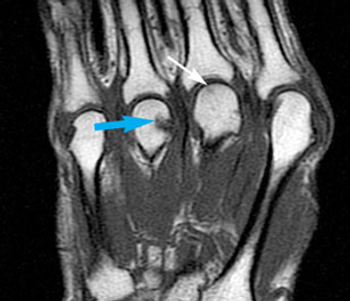

Could MRI detect the early signs of danger in patients who have not yet manifested symptoms of rheumatoid arthritis? New research suggests it can.